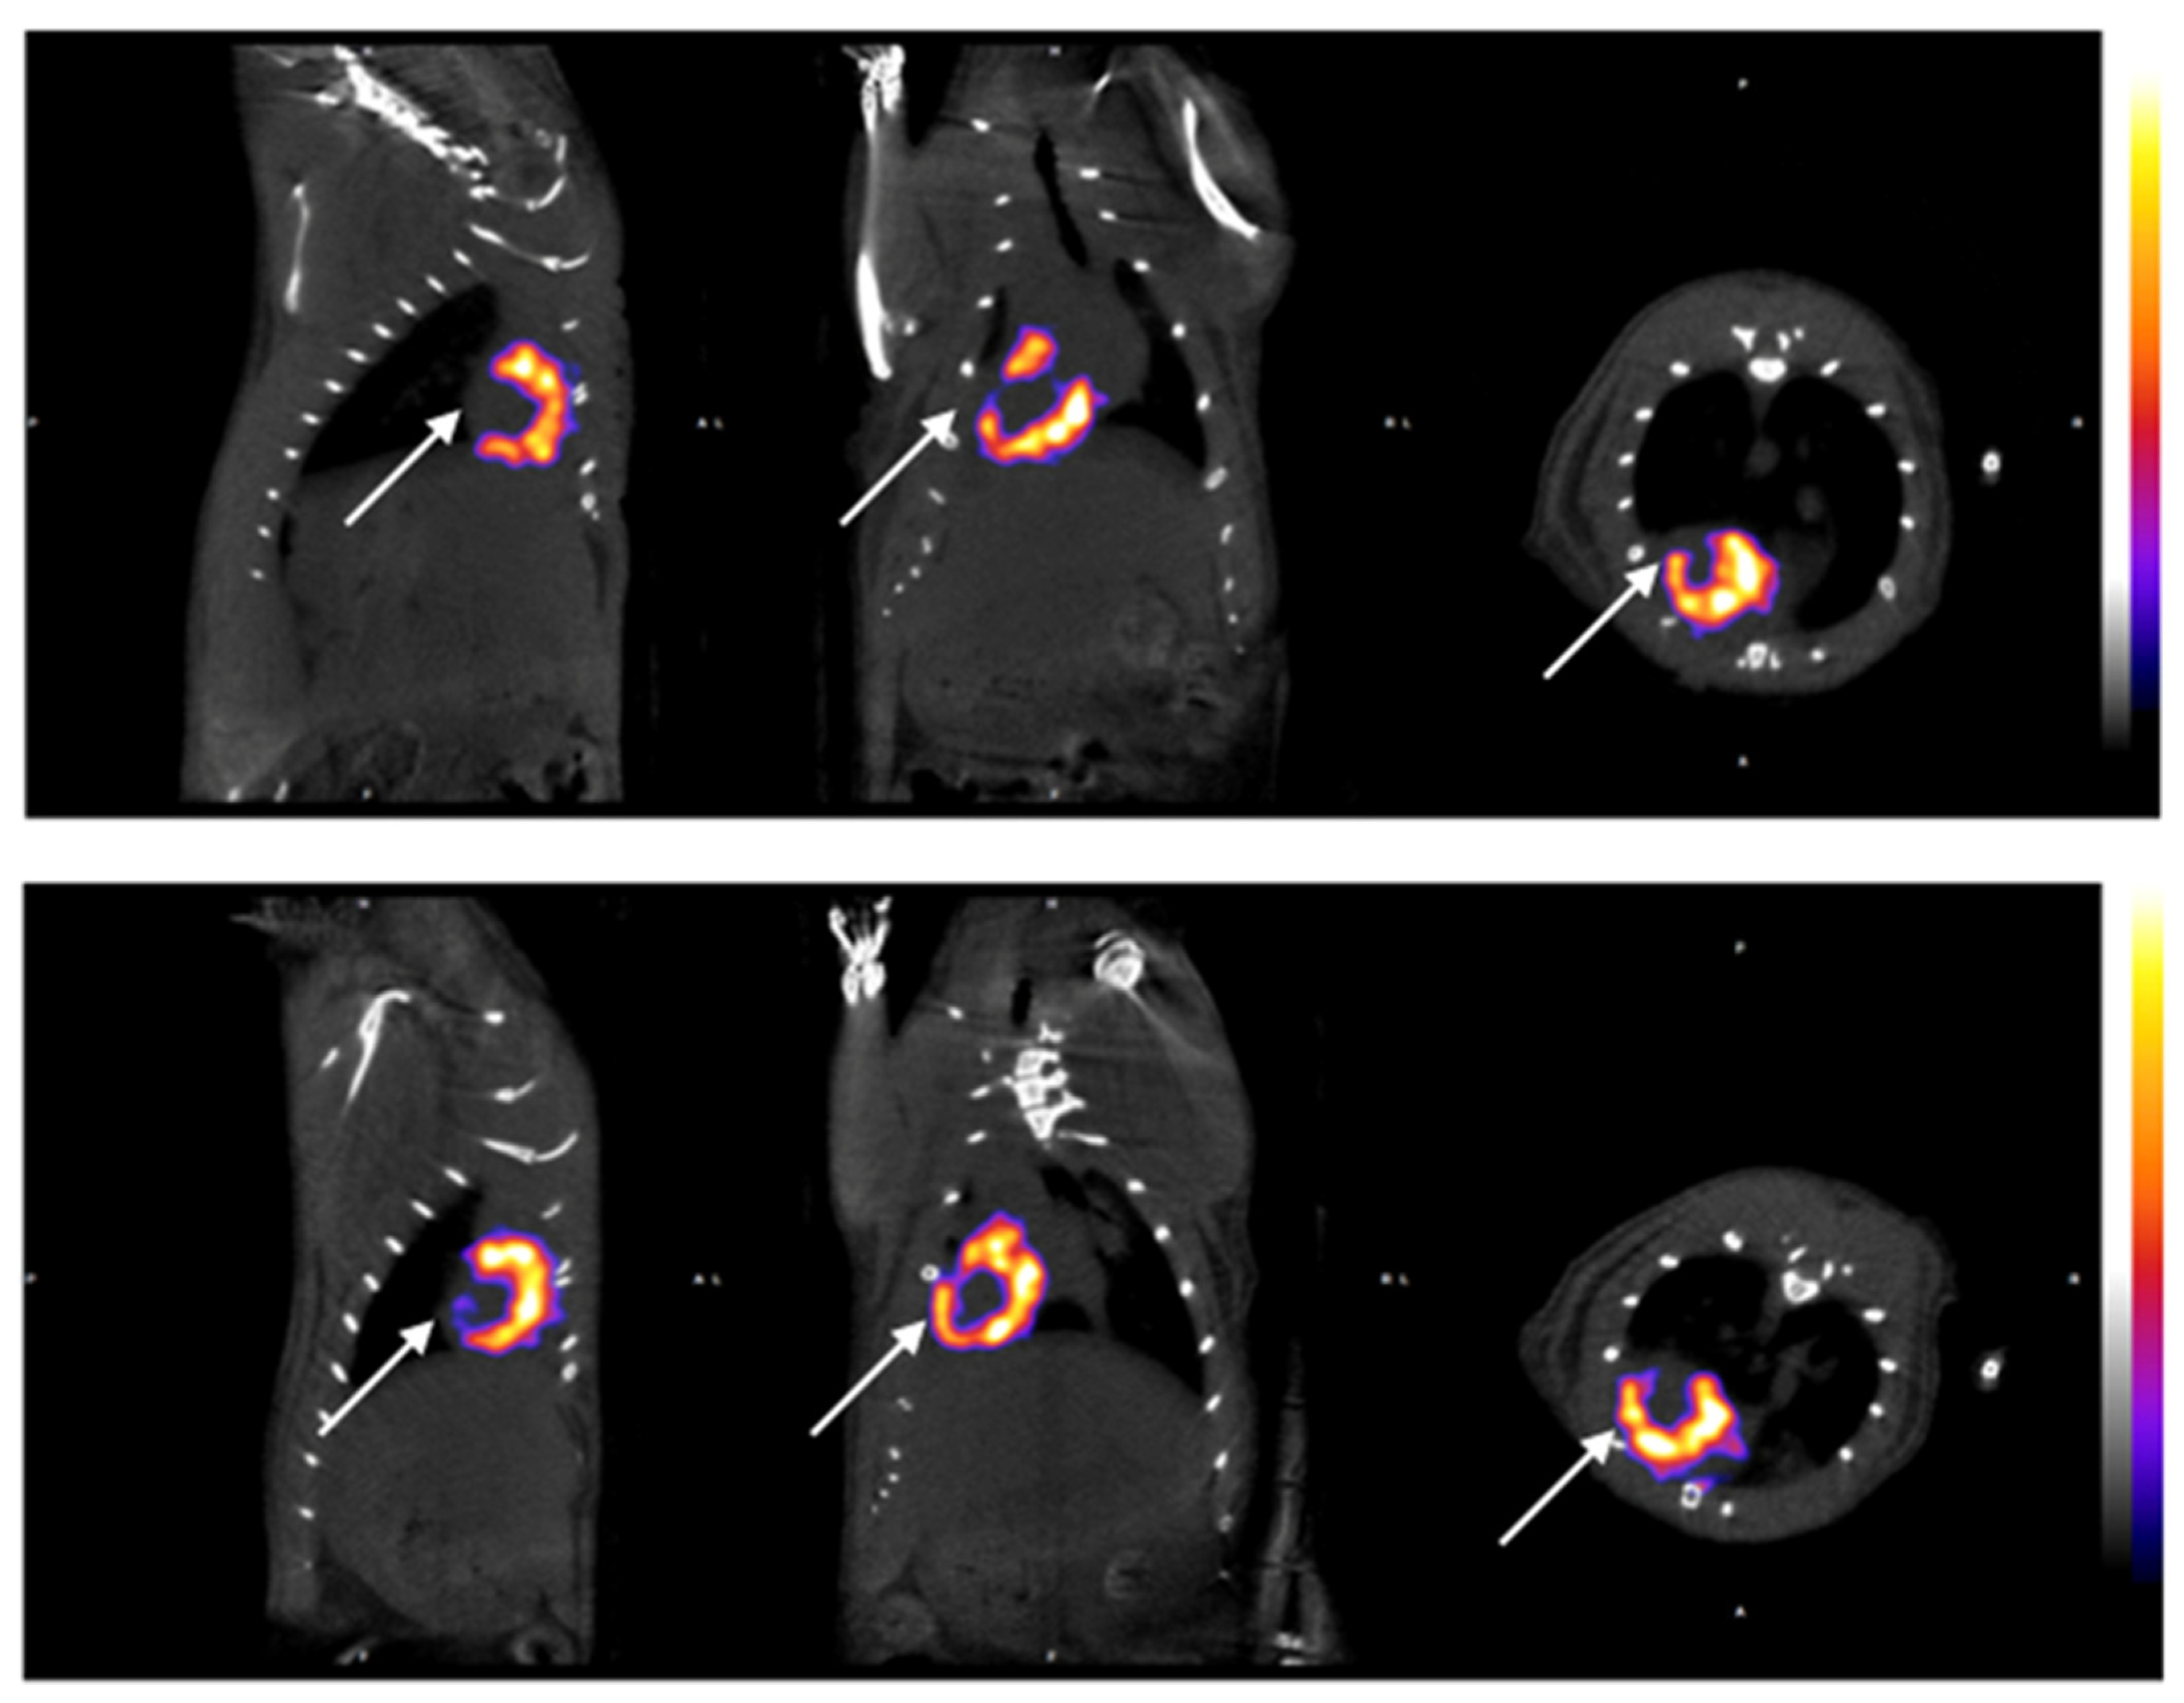

3.1. SPECT-CT Evaluation

| RATIO LV/RV (−7d) | 8.72 ± 0.36 | 8.77 ± 0.20 | 8.86 ± 0.22 | 0.480 |

| RATIO LV/RV (7d) | 8.69 ± 0.37 | 7.50 ± 0.24 * | 7.50 ± 0.29 * | <0.005 |

| RATIO LV/RV (14d) | 8.71 ± 0.34 | 7.59 ± 0.28 * | 8.00 ± 0.27 *,† | <0.005 |